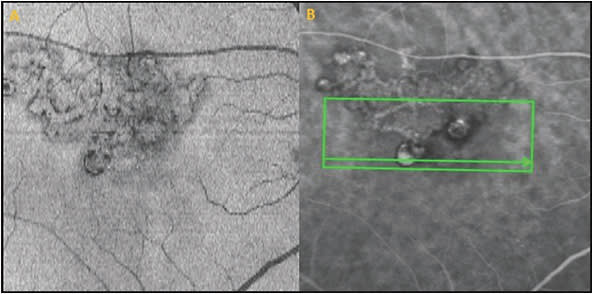

Indocyanine green angiography is often not available in many clinical settings around the world, including the United States, and when available, ICGA is often not performed, or expertise in reading the ICGA for PCV is not available. If ICGA is not available or not ordered, the diagnosis can be made using multimodality imaging with high specificity but lower sensitivity than ICGA. Optical coherence tomography angiography images the BVN well, although images of the aneurysmal or polypoidal lesions are poorer due to slower blood flow within the polypoidal lesions (Figure 3).18,19

En face OCT imaging also can often demonstrate the BVN and the aneurysmal dilations associated with PCV anatomically, but is again less sensitive than ICGA.18,20,21 However, lesions on en face OCT may appear larger than the CNV on ICGA, and this may be because the en face OCT images the whole vascular complex and the extracellular matrix surrounding the PCV complex, which may also elevate the RPE (Figure 4).18,20,21 Correlation of OCTA and en face OCT with B scan OCT increases the specificity of the diagnosis of PCV,18,19 because polypoidal lesions appear as inverted U-shaped lesions with heterogeneous reflectivity,3-4 whereas the BVN appears as a shallow elevation of the RPE above Bruch’s membrane (double line sign).15